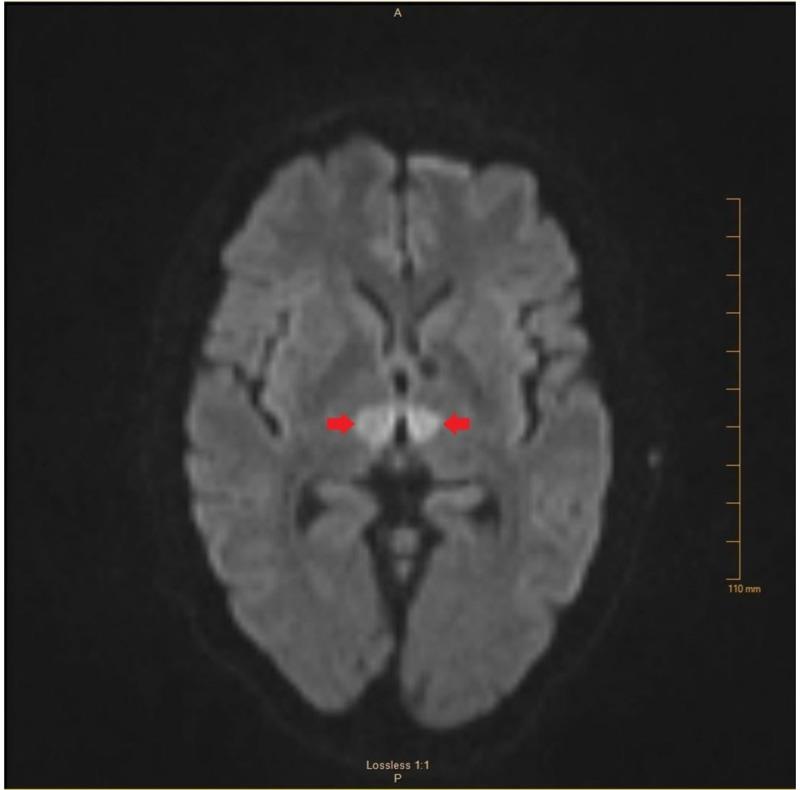

The artery of Percheron (AOP) is a variant of the paramedian thalamic vasculature that supplies blood to the medial aspect of the thalamus and the rostral midbrain. The presentation of an infarct in this territory varies widely and is often characterized by nonspecific neurological deficits, with altered mental status, decreased level of consciousness, and memory impairment being among the most common. AOP infarcts are often missed on initial computed tomography (CT) scan, and additional imaging is usually not done due to low suspicion for stroke in most cases. There have been an increasing number of reports of AOP infarction, illustrating the diversity of clinical presentations and the challenge this presents to clinicians in the acute setting. Lacking the classic signs of stroke, many of these patients experience a delay in recognition and treatment, with the majority of diagnoses occurring outside the tissue plasminogen activator (tPA) window. This case highlights the unusual presentation and diagnostic difficulty of a patient with an AOP infarct, and serves as a reminder to include thalamic pathology in patients presenting with vague neurological symptoms and no obvious signs of stroke.

佩谢隆动脉(AOP)是丘脑旁正中脉管系统的一种变异,为丘脑内侧和中脑前部供血。该区域梗死的表现差异很大,通常以非特异性神经功能缺损为特征,其中意识状态改变、意识水平下降和记忆障碍最为常见。AOP梗死在初次计算机断层扫描(CT)时常常漏诊,而且在大多数情况下,由于对中风的怀疑度低,通常不会进行进一步的影像学检查。关于AOP梗死的报道越来越多,这说明了临床表现的多样性以及在急性情况下给临床医生带来的挑战。由于缺乏中风的典型体征,许多此类患者在识别和治疗上出现延迟,大多数诊断发生在组织纤溶酶原激活剂(tPA)治疗窗之外。本病例突出了一名AOP梗死患者的不寻常表现和诊断困难,并提醒在出现模糊神经症状且无明显中风体征的患者中要考虑丘脑病变。